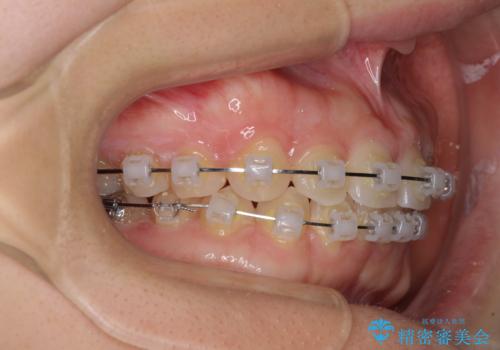

- 矯正装置

- クリアブラケット

ギリギリとなりましたが、結婚式直前にワイヤー装置を外すことができました。

ワイヤー装置除去後に細かい部分を短期間のマウスピース矯正にて仕上げました。